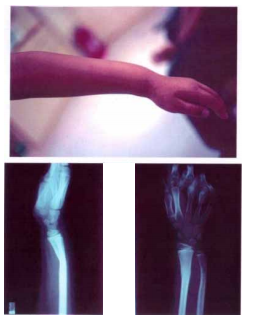

50 6 歲女童小馨,因玩耍跌倒,左臂撐地後發生劇 烈疼痛,家長緊急送醫後,經視診發現其前臂外 觀及 X 光片如右圖,此種變形應為下列何者? (A)餐叉 (B)湯匙 (C)沙鏟 (D)牛排刀

37 21 歲陳同學為某大學橄欖球校隊,某日於 比賽時,因奔跑撲球導致左手掌劇烈撞擊, 旋即發生劇烈腫脹疼痛,手指仍可活動, 但掌背腫脹異常。經送醫檢查發現 X 光如 右圖,則其診斷應為下列何者?